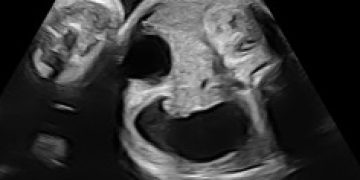

Cari soci, finalmente online le soluzioni dei casi del mese di Luglio Grazie a Carlotta Zorzi e Daniele Di Mascio!! Caso 1 - video [pdf-embedder url="https://www.sieog.it/wp-content/uploads/2024/07/risposta-Casodelmese_Luglio20241.pdf" title="risposta...